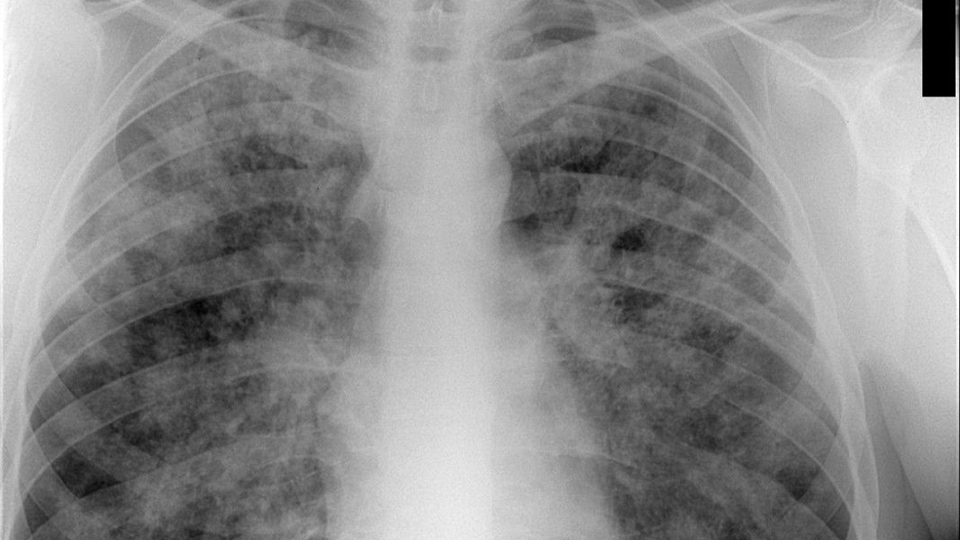

Рентгенологические изображения и синдромы патологии легких

Раздел: Кадры-подсказки